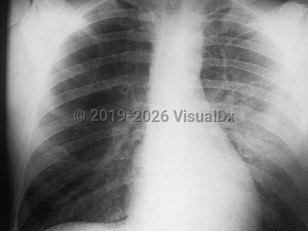

Primary pneumonic plague results in a severe fulminant illness with high fever, chills, headache, productive cough, chest pain, hemoptysis, extreme malaise, myalgias, tachypnea, tachycardia, and pneumonia. Gastrointestinal symptoms, including nausea, vomiting, abdominal pain, and diarrhea are also commonly seen. Secondary pneumonic plague is equally severe but arises later in the disease course of a patient initially presenting with bubonic or septicemic plague.

If not treated within 24 hours of onset, pneumonic plague rapidly progresses to acral cyanosis, respiratory failure, septicemia, circulatory collapse, and death. Untreated, the mortality rate of pneumonic plague approaches 100%. With treatment, the rate drops to 17%-20%.